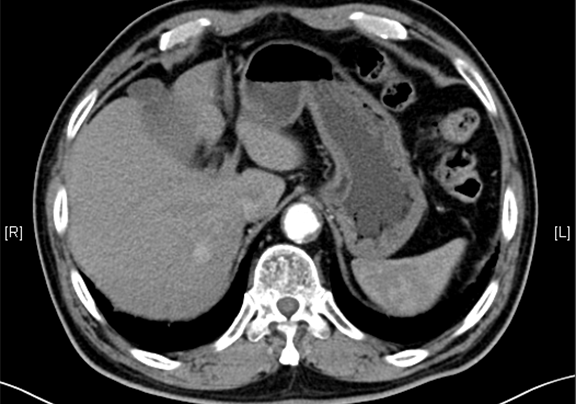

一般情况:CH-001-LT-000367,71岁男性患者,身高180cm,体重85.00kg,

主诉:体检发现肝占位性病变20天。

现病史:患者20天前于社区医院体检发现肝占位性病变,未诉不适,未予相关处理,6天前就诊于诸城中医医院,行上腹部增强CT:肝右叶后段肿块,考虑肝脏恶性肿瘤,仍未特殊处理,行消化系统超声示:慢性肝病,右肝结节,考虑肝Ca可能。

下腹部增强CT示:肝右叶血管瘤可能性大 ,双肺慢性炎症,双肾囊肿。

模拟手术操作,自动计算切除肿瘤体积。肝脏体积为1143ml,肿瘤体积为37.02ml,肿瘤体积为肝脏体积的3.2%,通过比对70-80岁正常肝脏体积为1118.08±190.14 ml,通过术前模拟手术,精准判断切除后剩余肝脏体积能耐受,避免肝衰竭发生。

1、(肝VII段)肝细胞肝癌,II级,大小3.5*2.5cm,以实片状及假腺型生长方式,侵达局部肝被膜,未累及肝断端;脉管癌栓(-,M0),神经侵犯(-),未见确切小胆管内癌栓及胆管壁侵犯;肿物周围未见卫星结节;2、慢性肝炎,G2S2。术后给予保肝、抑酸、化痰、静脉营养支持等治疗,恢复尚可。于2016-5-09出院。

随访8天,复查CT肝部分切除术后所见,肝右后叶斑片状低密度影。

术前CT检查:

动脉期

静脉期

平衡期